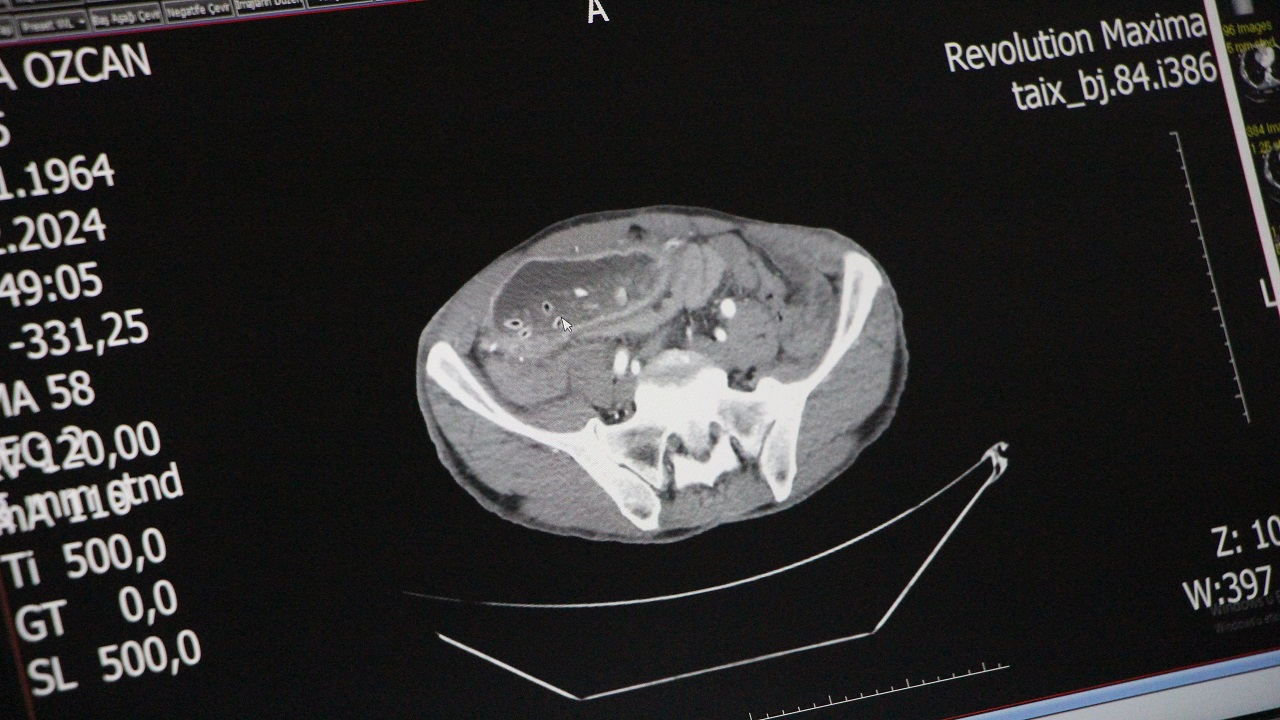

Amasya’da yaşayan 65 yaşındaki Hamza Özcan, çocukluğundan bu yana katı yemeklerden sonra kusma ve karın şişliği sorunuyla mücadele ediyordu. Özel Amasya Kolmed Hastanesi’nde yapılan ameliyatla midesinin 10 kattan fazla büyüdüğü ve karın boşluğunu sardığı tespit edildi.

Yapılan endoskopi ve tomografi çekiminin ardından gerçekleşen ameliyatında çıkış kısmı daralan midesinin 10 kattan fazla büyüyerek karın boşluğunu sardığı görüldü. Mide ve karaciğer arasında oluşan doku bandının mideyi ikiye ayırdığını gören Genel Cerrah Doç. Dr. Yavuz Pirhan, ince barsak ile mide arasına yeni bir kanal yaptı. Sağlığına kavuştuğuna çok sevinen evli ve 5 çocuk babası Özcan, “Canımın çektiği her şeyi yiyordum. Ama 10 dakika sonra geri çıkartıyordum. Çok rahatsız oluyordum. Ekmek yer gibi hap içiyordum. Şimdi anadan doğmuş gibi oldum” dedi.